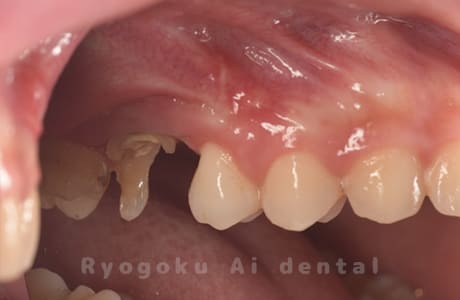

Case04

-

- 原因

- 重度カリエス、C3急化Pul

- 治療期間

- 約6ヶ月

- 治療内容

- 部分矯正、クラウンレングスニング、セラミッククラウン

- 治療費用

- 約350,000円

他院での説明で抜歯した後にインプラント治療を提案された患者さんです。虫歯が大きく、被せるための歯の長さが足りないため、埋まっている歯牙を引っ張り上げ、セラミックで被せたケースです。歯牙の状態も良好で、問題なく経過しています。